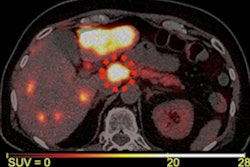

Image courtesy of the Journal of Nuclear Medicine.Tumors were defined as uPAR positive by two experts based on standardized uptake values (SUV) of the tracer in the lesions. Patients were followed for at least one year to determine their progression-free survival and overall survival.

During follow-up, 59 patients (62%) experienced progressive disease and 28 patients (30%) died. High uPAR expression in tumors was seen in 68% (n = 65) of all patients and in 75% (n = 18) of patients with aggressive disease. High uPAR expression carried a hazard ratio of 1.87 for progression-free survival and 2.64 for overall survival (p < 0.05 for both), according to the findings.